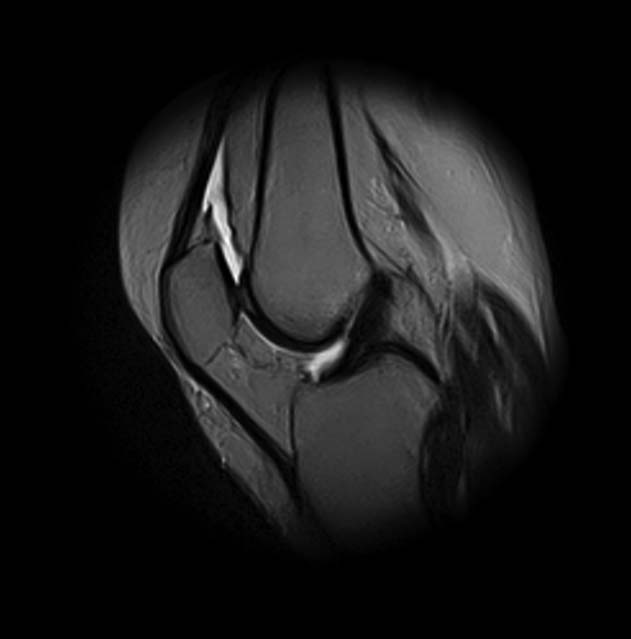

[Ortho] Показания для артроскопии

1. травма 5 лет назад - "ударилась коленом", с тех пор боли в суставе

3. стандартные рентгенограммы с небольшими изменениями - сужение

медиальной суставной щели

4. вес пациентки 80 кг, рост 165

5. сустав клинически стабилен